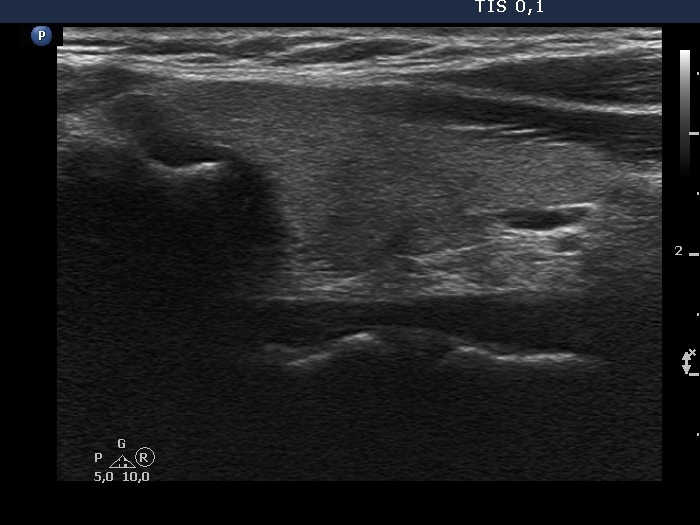

Thyroid cancers - case 327 (ultrasonographic picture 5)

Left lobe, longitudinal scan. There is a minimally hypoechoic area in the dorsal part of the lobe. According to this, no discrete lesion was described on histopathology.